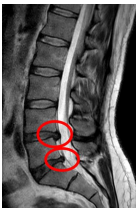

Hernie Discale

Compression radiculaire postérieure causant des symptômes dans le dermatome correspondant.